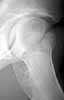

I believe this patient has anterior hip impingement caused by a retroverted acetabulum. This is seen on the submitted AP x-ray by observing the overlap of the anterior wall and posterior wall. In an acetabulum with "normal" version, the anterior wall shadow meets the posterior wall shadow at the superio- lateral aspect of the acetabulum, and they do not overlap as you follow the lines inferiorly. In an acetabulum with retroversion, the two shadows cross over the femoral head, making a figure 8 pattern.

To further confirm this, obtain a full AP pelvis film and a false profile view of both hips. In addition, the patient has an element of hip dysplasia, seen by his decreased center edge angle. On physical exam, his pain will be reproduced by hip flexion, adduction and internal rotation, when the anterior surface of the femoral neck impinges on the anterior labrum and wall. An MRI may show hypertrophic changes in the femoral neck. I also recommend a gadolinium MRI hip arthrogram to ensure there is no significant labral pathology.

Here are some pictures from a case where the femoral head was surgically dislocated and trimmed for acetabular and femur impingment syndrome.

The technique is described by Ganz and Mast as a digastric approach (trochanter flip osteotomy) to the hip joint without destroying blood supply to the femoral head. The approach may also be applied to some acetabular fractures.